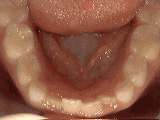

missing lateral incisors

This patient's lateral incisors were congenitally missing. She had braces for twenty months to move the teeth into the correct position, then the missing teeth were replaced with bonded "Maryland" bridges.